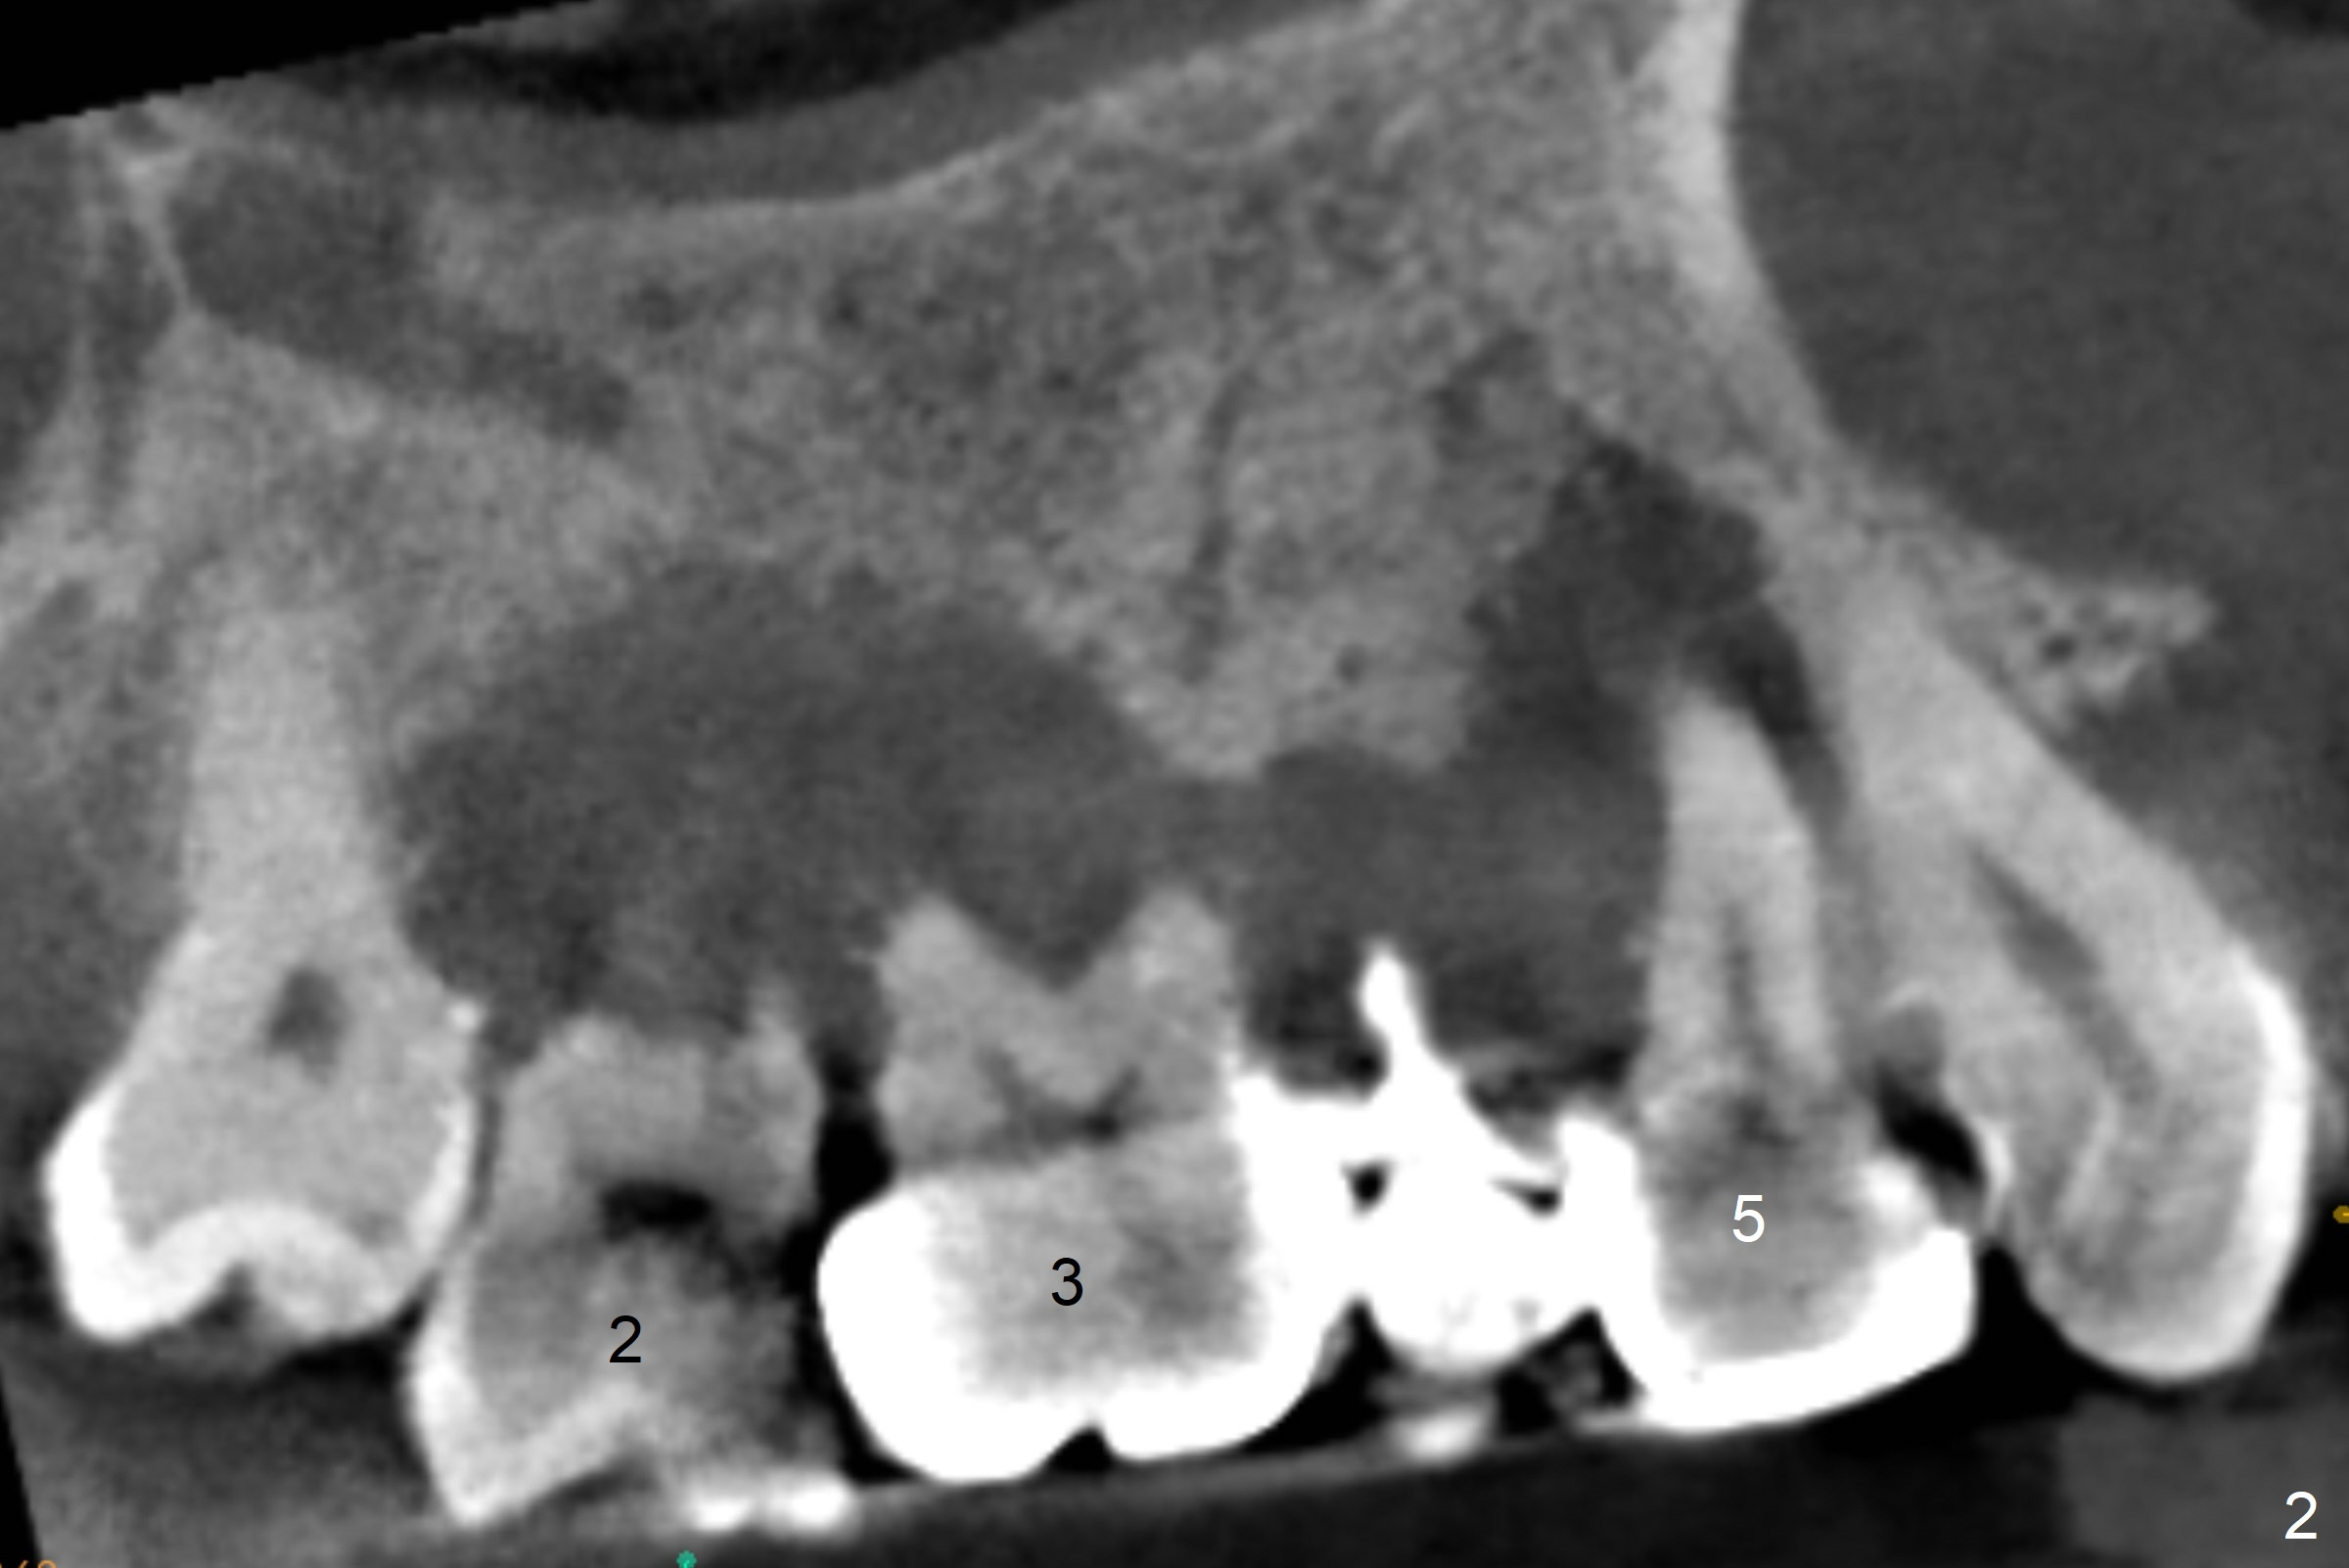

A 45-year-old man will return for #2, 3 and 5 extraction and implants (Fig.1,2). Take PAs for and Reline #7,9,11 provisional crowns and fabricate #11-13 temporary FPD if #15 implant is still unstable (5 months postop). Establish normal occlusal contact.

Extract #2 or remove #3-5 FPD first whichever is looser. Use the other as reference guide. Place Osteogen plug in the palatal socket of #2 ad 3 (Fig.3,4 yellow box) and allograft around the implants (red circles).